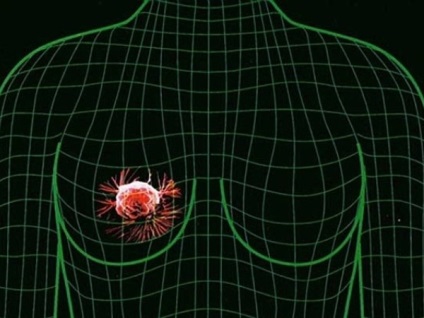

Fibroadenomatosis este un proces în care imaturi țesăturile formă de celule, localizate în glandele mamare, extinde - și raportul dintre țesutul conjunctiv și epitelial au schimbat foarte mult, iar fibrotic apar, chistice și alte modificări.

În cazul unor modificări ale glandelor mamare, tratamentul problemei depinde de forma sa. În cazul în formațiuni foarte mari de tratament chirurgical, mastectomie. Acest lucru va evita, de asemenea, dezvoltarea potențială a unei tumori maligne. Dacă totul nu este atât de gravă, se efectuează medicație. hormoni tiroidieni aplicate, progesteron, contraceptive și alte medicamente care sunt numiți de către medicul individual. Nu este de ajuns să fie tratate, este important să se mențină monitorizarea constantă a zonelor cu probleme.

Acum, că ne înțelegem cum există fibroadenomatosis sân decât este caracterizată prin faptul că este vorba și cum să-l trateze, pentru a rezuma un rezumat al rezultatelor. De obicei, în cazul în care nu fibroadenomatosis rula și monitoriza, nu este periculos pentru ei, dar indică prezența unor probleme hormonale în organism. Uneori, sub masca de fibroadenomatosis poate ascunde oncologie, astfel încât acesta va urma cu siguranță și cu atenție, la prima suspiciune puternică a unei probleme, contactați medicul dumneavoastră.